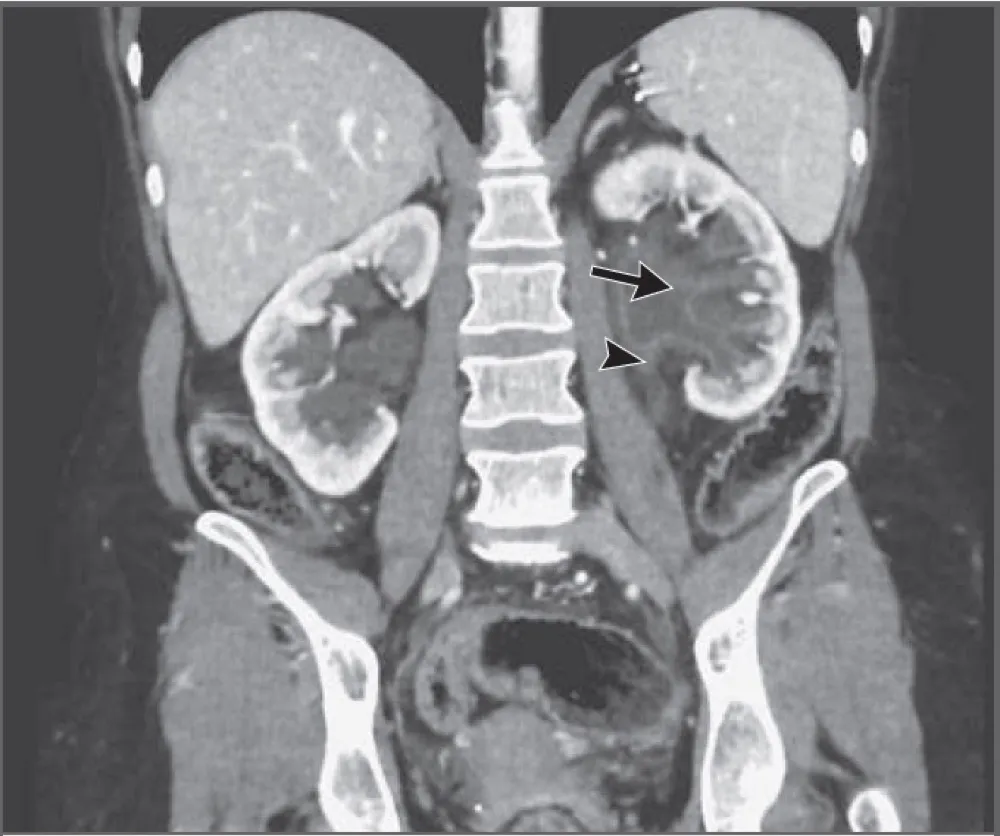

IRA + Icterícia: Um Caso que Exige Investigação Detalhada

IRA + Icterícia: Um Caso que Exige Investigação Detalhada